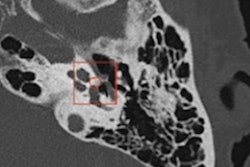

In a population study involving 997 participants from the Robinsca CAC screening clinical trial in Europe, the company's AI-based Aview CAC software yielded 99.2% accuracy for categorizing risk compared with an experienced reader's interpretation of the low-dose CT exams, according to the researchers from the Institute for Diagnostic Accuracy (iDNA) at the University Medical Center Groningen in the Netherlands.

"The deep learning-based software for automatic CAC scoring can be used in a cardiovascular CT screening setting with high accuracy for cardiovascular risk categorization and initiation of preventive treatment," said senior author Dr. Matthijs Oudkerk, PhD, in a statement from Coreline.